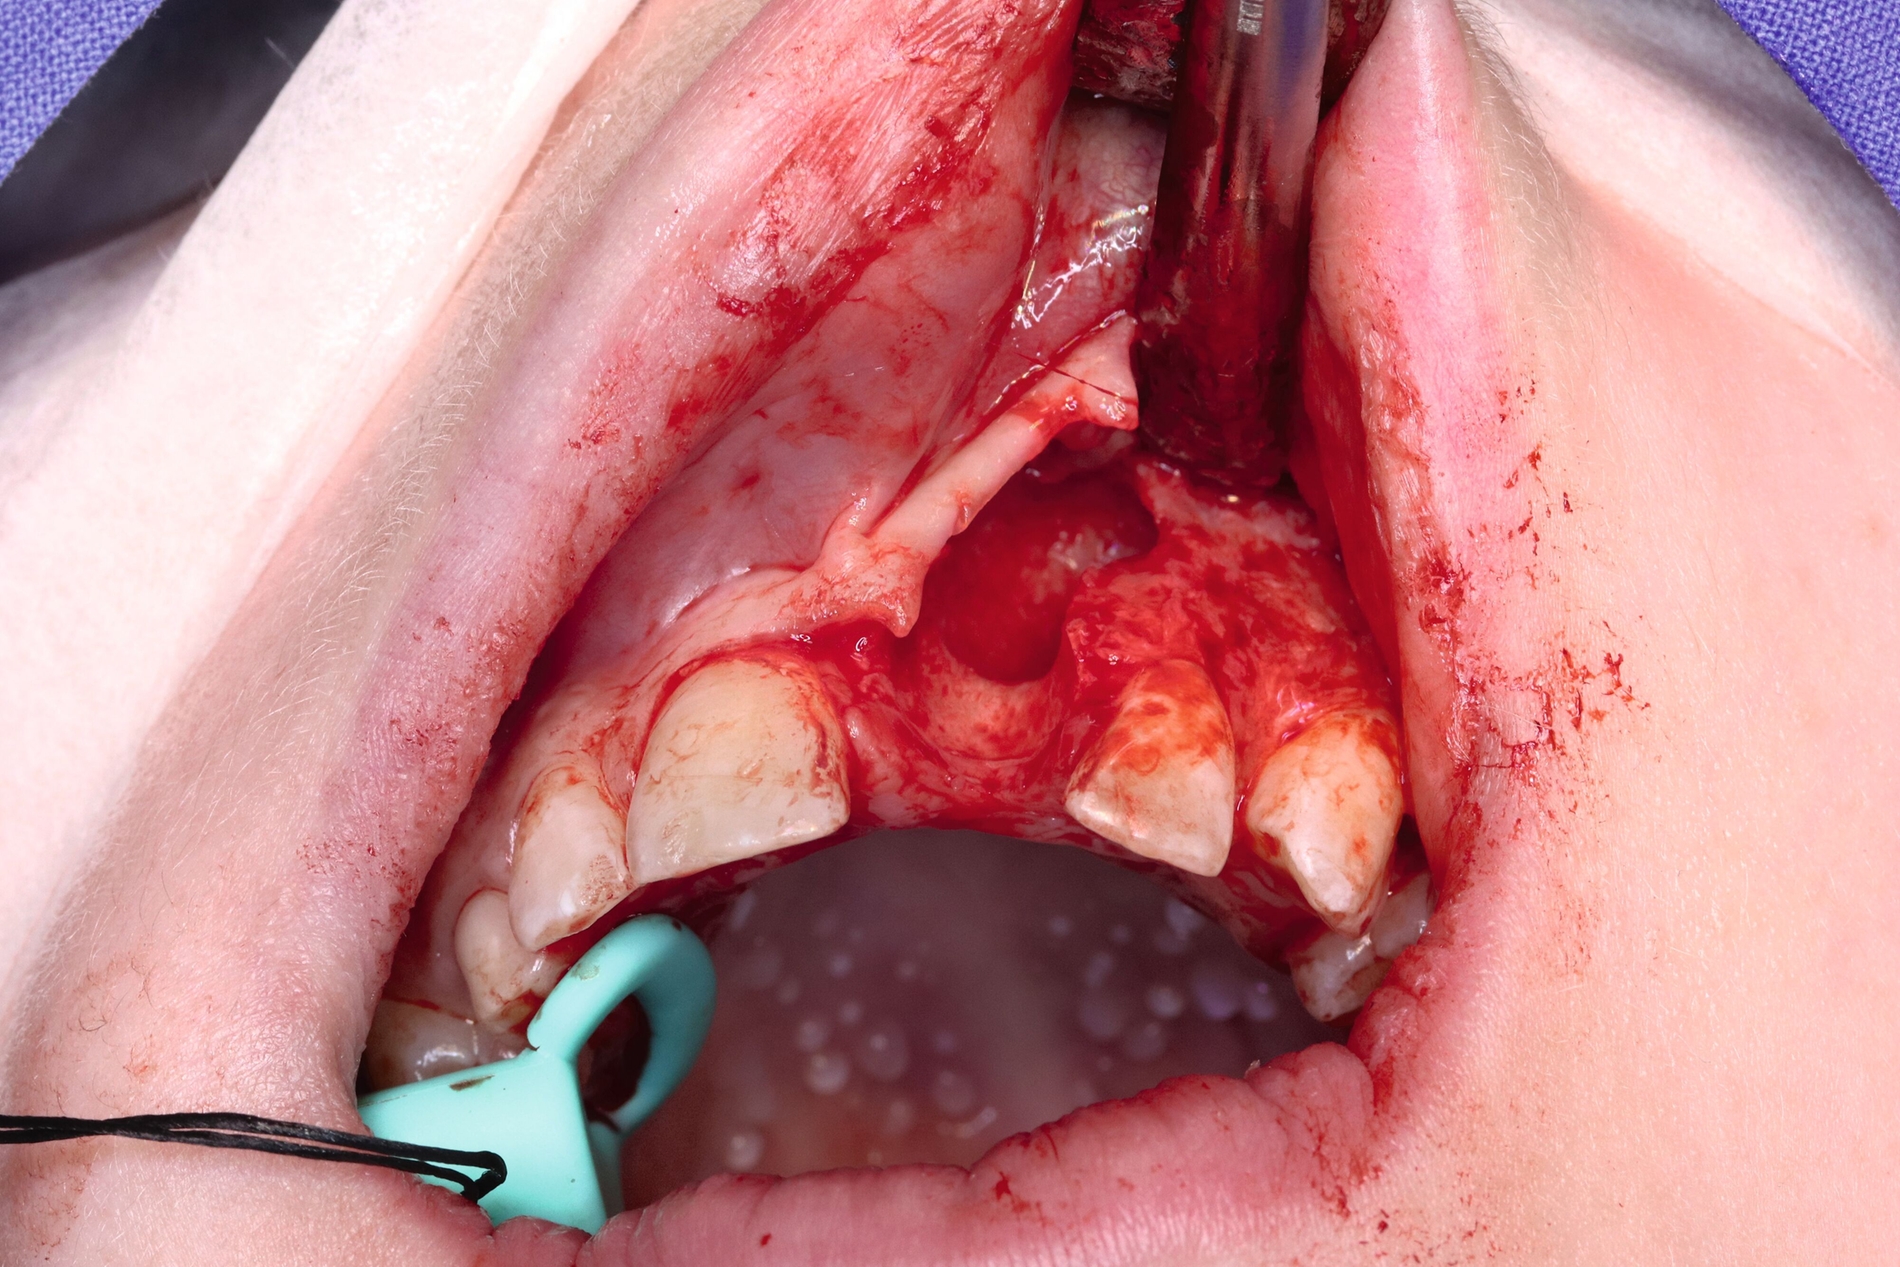

Zwei Jahre nach einem komplexen Zahntrauma mit komplizierter Kronenfraktur 21 und endodontischer Versorgung stellte sich eine elfjährige Patientin mit nun ausgedehnter apikaler Beherdung am Zahn 21 bei uns vor (Abbildung 1). In ihrer Krankengeschichte hatte die Patientin im Alter von vier Jahren eine Leukämie überwunden. Es wurden keine weiteren gesundheitlichen Probleme angegeben. Im OPG zeigt der Zahn 21 eine periapikale Aufhellung im Sinne einer Parodontitis apicalis chronica mit nun akuten klinischen Schmerzen (Abbildung 1).

Zur weiteren Abklärung wurde eine dreidimensionale Aufnahme durchgeführt (DVT). Dabei bestätigte sich die erhebliche Osteolysezone im apikalen Bereich des vormals traumatisierten Zahnes 21. Der Zahn 13 stellt sich hoch verlagert am Nasenboden dar, während es bei dem persistierenden Milchzahn 53 zu einem natürlichen Lückenschluss in regio 13 gekommen ist (Abbildung 2).